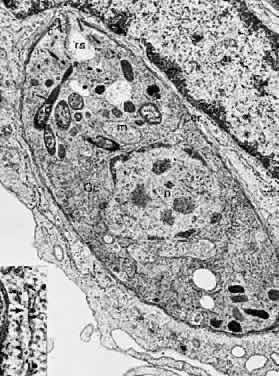

The lesions of ocular toxoplasmosis (Fig. 1) can be important causes of blindness, particularly if they involve the macula, the papillomacular bundle, or the optic nerve. Occasionally, a large peripheral lesion casts off so much inflammatory material into the overlying vitreous humor that vision is affected. In some cases, inflammation initiates organization of the vitreous body; on subsequent contraction of the fibrous bands within this inflammatory mass, tearing of the retina may occur and retinal detachment may ensue.

Fig. 1. The characteristic lesions of toxoplasmic retinochoroiditis in the fundus of an adult. Black arrow denotes active lesion with indistinct borders. White arrow denotes healed “satellite lesions.” (O'Connor GR: Ocular toxoplasmosis. In Locatcher-Khorazo D, Seegal BC (eds): Microbiology of the Eye. St Louis, CV Mosby, 1972.)